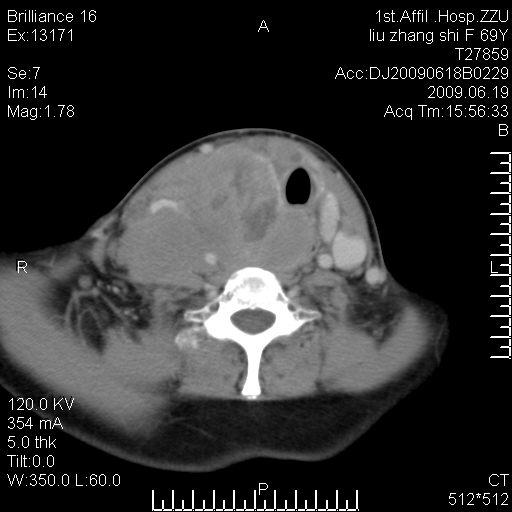

标题: CT26782:女,69岁,颈部占位,3天后公布病理结果。

【病理证实系列】女,69岁,颈部占位,有病理结果,3天后公布。(由于病例时间较久,临床资料不全,请网友见谅)本系列将有几百种常见、少见及罕见病例,均经病理证实。病例资料来自郑州大学第一附属医院。与网友共享,本人有空就发。

甲状腺癌并颈部淋巴结转移。感谢楼主的良苦用心,谢谢。

甲状腺癌并颈部淋巴结转移。

需与鼻咽癌鉴别!

支持甲状腺癌广泛侵及周围结构并颈部淋巴结转移。

鉴别:淋巴瘤、恶性神经源性病变、恶性纤维组织细胞瘤。

病理结果:颈部非霍奇金淋巴瘤。